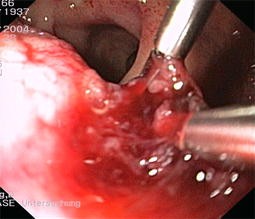

Abb. 2